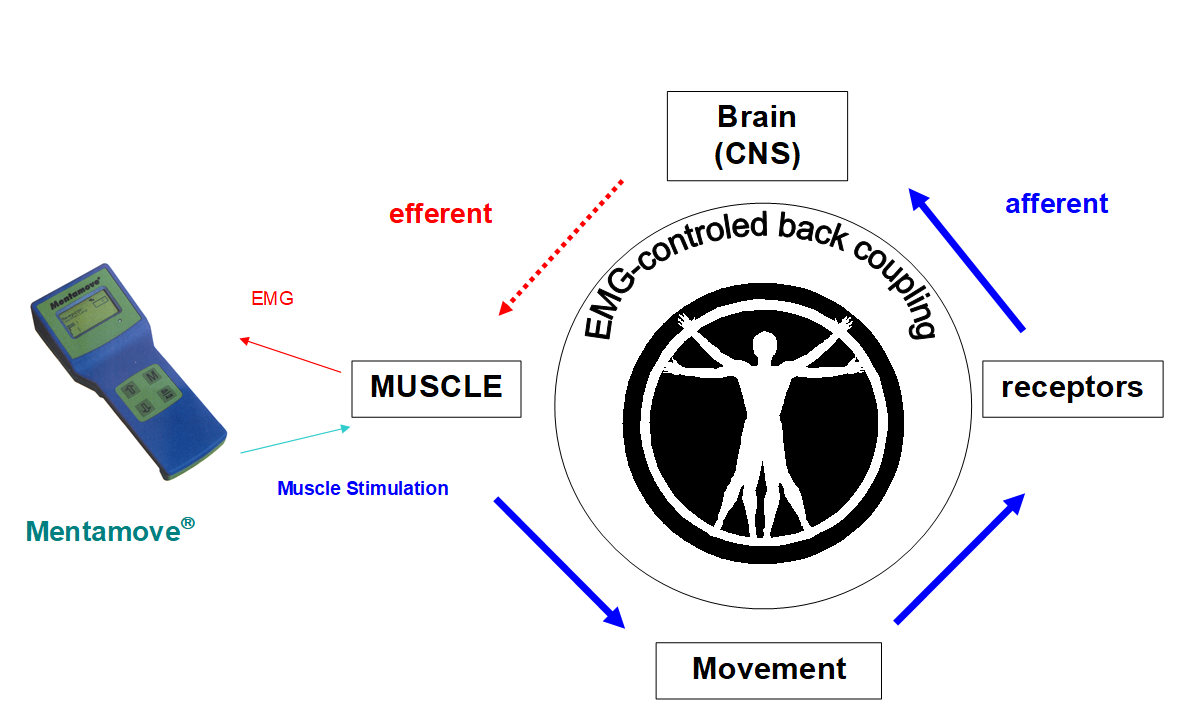

Background: The “Brain Efficiency Training” Mentamove® is a neurorehabilitation method is used for the rehabilitation after various brain lesions. If the motoric activities are mentally practised by the case, the real movement gives a reorginasation to the brain due to neuroplastisity. EMG-initiated muscular stimulation gives is an effect mainly used in the treatment of stroke patients. It is a combination of muscular stimulation with medium frequency sine current and a biofeedback process (Fig 1). But never have been used at the periferic nevre lesions and cranial nerve lesions before. Our opinion comes from the biofeedback coupling theory and if is the method works trully it may be give the positive effect like central nervous system for recovery. The efferent and afferent ways of the cranial nerves work differently from other peripheric nerves. The motor fibers (efferent) of the m. palpebrae sup. have two ways N. Oculomotorius (III) (Fig 2) and Cervical Sympathetic Chain (Sup. Cervical Ganglion) (Fig 3). The M. Orbicularis Oculi and M. Fontalis innervates with efferent fibers of the N. Fascialis (VII), this cranial nerve comes from the facial motor nuclei of the brain stem. The Oculomotor nerve also carries the motor (efferent) fibers to the (m.rectus medialis, m. sphincter pupilla) from nuclei of the brain stem and mesensephalon. These nuclei are under the mental motor control of the temporal (fascial) and frontal (eye conjugated movements) lobes bilaterally. But the sensorial ways (afferent) works with N. Trigeminus (V) and its sensorial nucleus is in the brain stem. Our theory bases on the incomplete motor oculomotor nerve fibers injury and healthy trigeminal nerve fibers. The parasympathetic (efferent) fibers come with oculomotor nerve to the ciliary ganglion and to the sphincter pupilla. These fibers placed superficially on the III. Nerve. When the nerve affected partially or totally the pupilla dilatation and ptosis were seen. If the injury affects the deep fibers of the III. nerve the medial rectus have been paralysed. It is urgent for intracranial surgical decompression (1, 2, 3). There is no prior documented case treating on the cranial nerve lesions with Mentamove®. But our opinion comes from the biofeedback coupling theory and if is the method works trully it may be give the positive effect like central nervous system for recovery (Fig 1). Sometimes a big aneurysm on the posterior communicant artery may compress the III. nerve, this clinical data may be seen spontaneously. Also during the surgical procedures for these aneurysms the III. nerve may be injured.